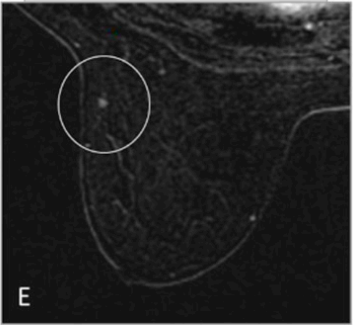

AI-Based Analysis of Temporal MRI Sequences for Early Detection of High-Risk Breast Cancer Signs in Mutation Carriers

Using AI-based analysis on temporal MRI sequences to identify high-risk signs of breast cancer in mutation carriers earlier than traditional methods